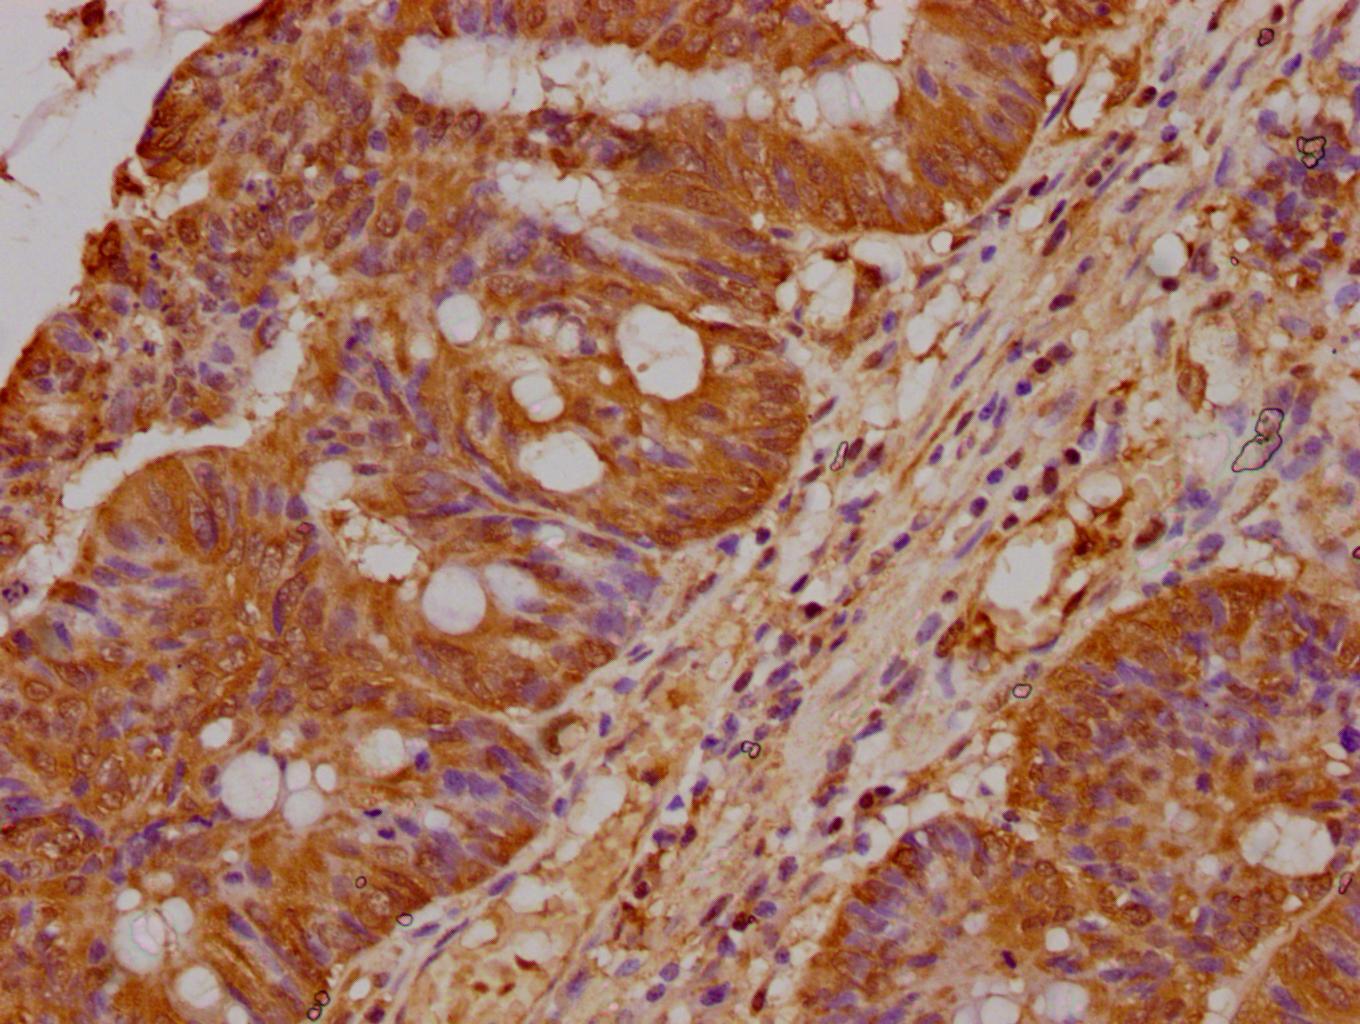

- Immunohistochemical analysis of PRAMEF18 in paraffin embedded human colon cancer using a PRAMEF18 polyclonal antibody (Product # PA5-98083) at a dilution of 1:400. After dewaxing and hydration, antigen retrieval was mediated by high pressure in a citrate buffer (pH 6.0). Section was blocked with 10% normal goat serum 30min at RT. Then primary antibody (1% BSA) was incubated at 4°C overnight. The primary is detected by a biotinylated secondary antibody and visualized using an HRP conjugated SP system.